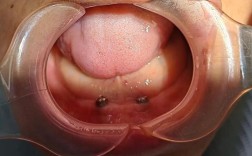

- 目标: 通过在下颌骨内植入多颗种植体,在其上部安装一个固定的、不可摘戴的牙桥(通常称为“全口固定义齿”或“种植桥”),替代所有缺失的下牙。

- 修复方式: 在这4颗(或6、8颗)种植体上,通过一个精确制作的金属支架(或全锆支架),连接12-14颗牙冠,形成一整排固定的牙桥。

- 原理: 在下颌缺牙区的每个位置(或大部分位置)植入一颗种植体,数量通常在6-10颗或更多,每颗种植体上安装一个基台,然后在基台上连接牙冠或分段桥,最终连成一整排固定桥。

二期手术 (暴露种植体):

骨结合完成后,需要一个小手术切开牙龈,暴露种植体顶部的连接结构(基台连接部分)。

基台安装和取模:

- 将愈合基台换成用于支撑牙冠的最终基台。